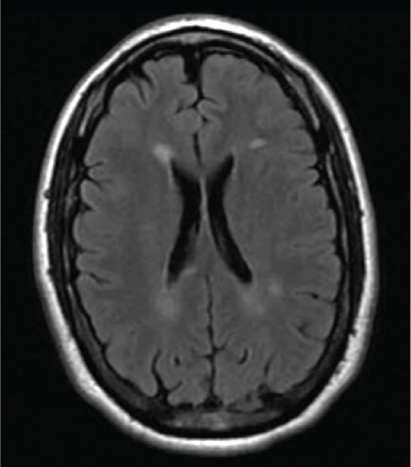

At 3-month follow-up on glatiramer acetate, he reported sensory symptoms, thought to be a clinical relapse. An MRI showed new nonenhancing MS lesions in the cerebrum and brainstem (Figure 3 and Figure S2). Concurrent chest CT showed a decrease in pulmonary nodules despite ongoing cough and sputum production. Priority was given to optimizing MS therapy as the pulmonary cryptococcus seemed to be resolving. Taking into consideration his breakthrough demyelinating disease, the need for higher-efficacy DMT with a different mechanism of action, yet still not strongly immunosuppressive, was prioritized. Dimethyl fumarate therapy was initiated. Three months after starting dimethyl fumarate the patient reported being at his neurologic baseline. At 6 months, he had no new symptoms, and neurologic examination findings were improved; the only findings were old findings of right eye decreased vision with afferent pupillary defect and left upgoing toe. The MRIs of the neuroaxis showed no new lesions. Chest CT showed mild improvement. The patient continues to take dimethyl fumarate.

Brain magnetic resonance image 3 months after discontinuing fingolimod use, initiating glatiramer acetate therapy, and reporting clinical relapse in interim